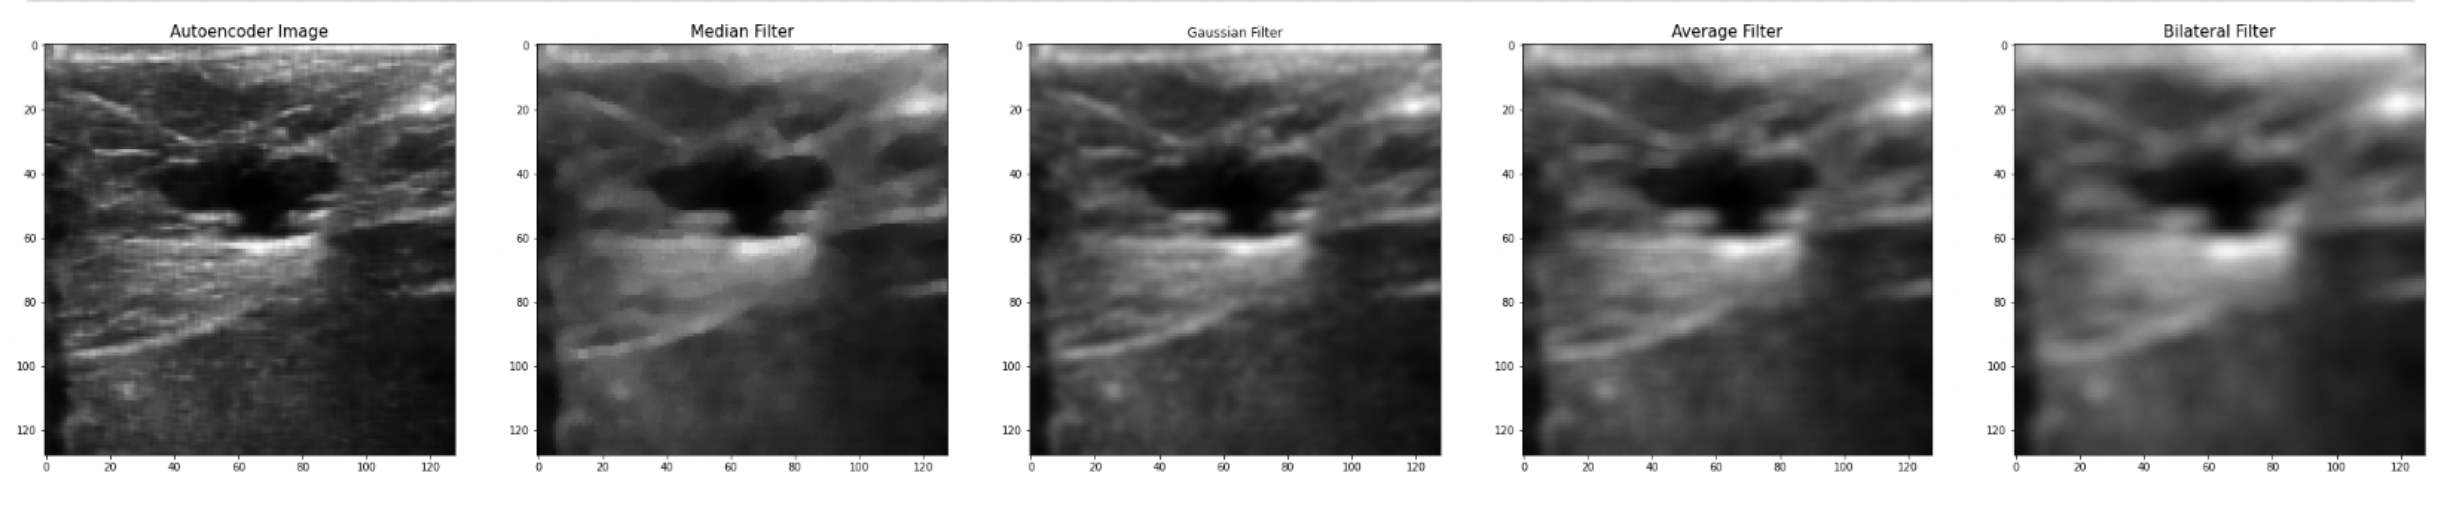

During the evaluation part, we compare the results of the CNN autoencoder with the old filter techniques. The first filtering technique is the Gaussian filter which is a low-pass filter that is used for noise reduction and adds blurring in regions in the image. The main parameter in this type of filtering is the standard deviation parameter. Increasing or a higher standard deviation the more effective in reducing the noise, but it may also lose small details in the image, which is one of the main limitations in previous papers. The second filtering technique is the Median filter, which is a non-linear filter, and it works by replacing each pixel value with the median value within a local neighborhood. It’s very effective in removing salt and pepper noise, it doesn’t lose important details, and it does not blur the image. The third filtering technique that we use to compare our results is the Average filter, and it works by replacing each pixel with the average value of its neighboring pixels. The last filtering technique is the Bilateral filter, which is a non-linear filter. It works by taking the weighted average neighbor pixels, and the weight depends on the distance between the pixel itself and the center pixel. It’s an effective way to remove noise while preserving the edges and small details.

The best PSNR results we have reached so far, as mentioned earlier is (PSNR = 30.44), while at the Median filter, it was (PSNR = 25.362), Gaussian filter (PSNR = 27.541), Average filter (PSNR = 24.934), and Bilateral Filter (PSNR = 23.675), as shown in details at table II, and we can conclude from these results that the CNN Autoencoder is better that the other filtering techniques by 20.02%, 10.52%, 22.08%, and 28.57%, respectively. These results came at an epoch size of 30, batch size of 16, and 256 filters in each of the CNN Layers using the combined dataset which consists of 1568 breast ultrasound images. Below is the training vs validation loss graph , as well as the output image compared to old filtering techniques.

While the best MSE results we have reached so far, is (MSE = 0.0009), while at the Median filter, it was (MSE = 0.0022), Gaussian filter (MSE = 0.0017), Average filter (MSE = 0.0028), and Bilateral Filter (MSE = 0.0034) and we can conclude from these results that the CNN Autoencoder is better than the other filtering techniques. These results came at an epoch size of 50, batch size of 16, and 256 filters in each of the CNN Layers using the combined dataset which consists of 1280 breast ultrasound images, also the same MSE came at an epoch size of 30, batch size 16, and 256 filters in each of the CNN Layers, and a dataset of size 1568 ultrasound images.

The best SSIM results we have reached so far is (SSIM = 93.5%) while at Median filter it was (SSIM = 78.5%), Gaussian filter (SSIM = 87.1%), Average filter (SSIM = 76.9%), and Bilateral Filter (SSIM = 70.7%) and we can conclude from these results that the CNN Autoencoder is better than the other filtering techniques. These results came at an epoch size of 30, batch size of 16, and 256 filters in each of the CNN Layers using the combined dataset which consists of 1568 breast ultrasound images.

Another limitation that was fixed is not losing tiny details, because as shown in the resulting image all details are still shown; however, using old filtering techniques will lead to loss of data due to lowering image resolution. Also, a problem that some of the papers faced was that they used a low-processor computer which limited their training, but using Kaggle GPU it was able to solve this issue and reach an epoch size of 300.